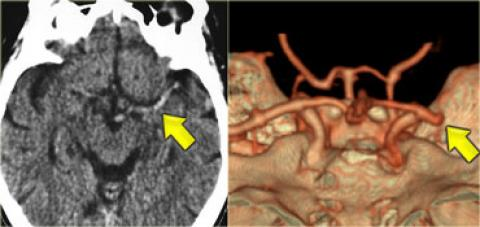

Hình ảnh giảm tỷ trọng nhân bèo, thường liên quan đến nhồi máu động mạch não giữa MCA

Hình ảnh tắc động mạch não giữa MCA bên phải trên CTA